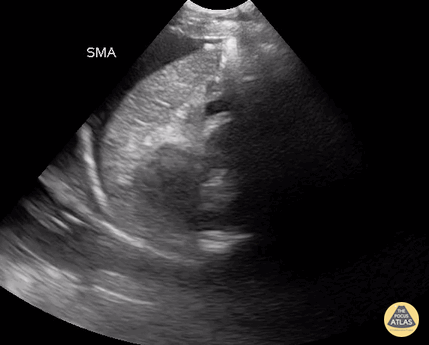

Positive FAST with free fluid in the LUQ. Note anechoic fluid in the sub diaphragmatic recess between the diaphragm and the spleen. Contributor: Antonio Riera, MD